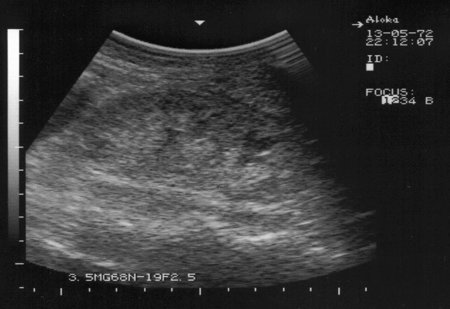

Амилоидоз почек. Renal amyloidosis

Диагноз доказан морфологически.